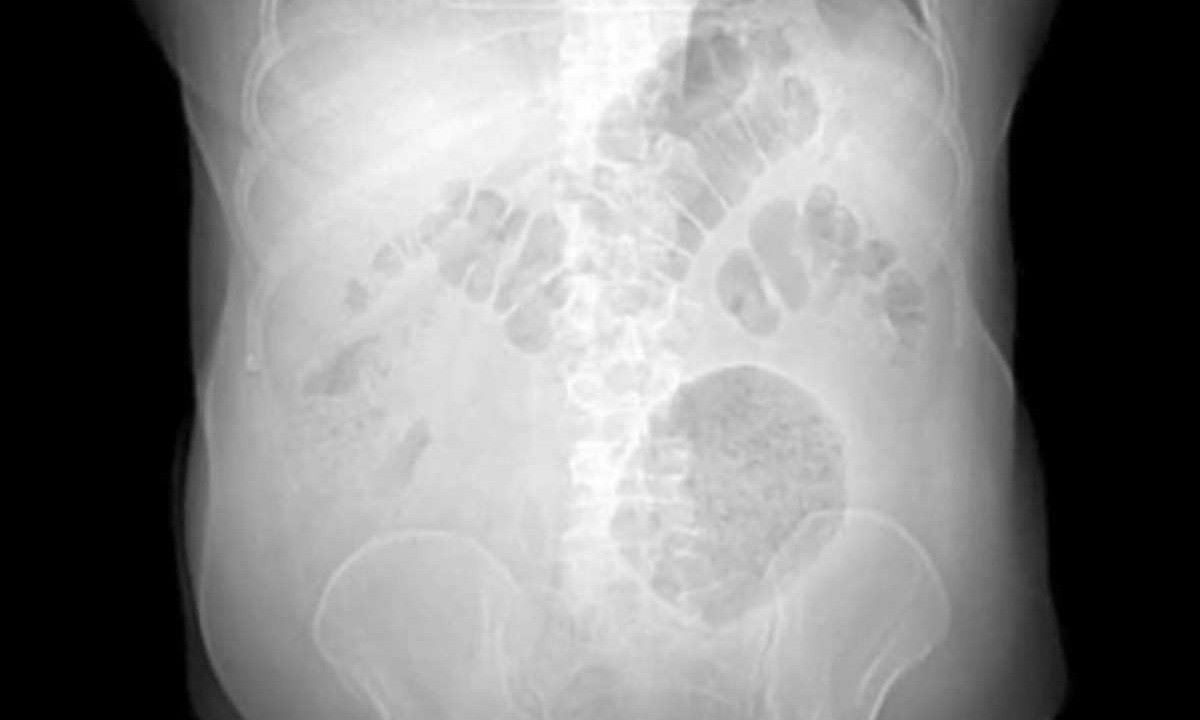

Descoberta e Tratamento do Caso O paciente, um homem de 62 anos, procurou o hospital com queixas de dores abdominais e perda de peso persistentes. Após exames, incluindo tomografia computadorizada, foi descoberto um divertículo inflamatório medindo 13 x 12 x 10 cm na região abdominal. Para referência, a dimensão média dessa condição varia entre 4 cm e 9 cm de diâmetro.

Procedimento Cirúrgico e Recuperação Uma semana após os exames iniciais, uma cirurgia de laparotomia exploradora foi realizada, confirmando a presença da massa inflamatória no cólon sigmoide. Felizmente, o paciente teve uma recuperação tranquila, recebendo alta quatro dias após o procedimento.

Dados sobre o Divertículo Gigante do Cólon De acordo com a Sociedade Brasileira de Hepatologia, o DGC afeta homens e mulheres igualmente, com maior incidência em indivíduos entre 35 e 90 anos, com média de 65 anos. Os métodos de diagnóstico incluem exames de imagem, como tomografia computadorizada e ressonância magnética, enquanto o tratamento cirúrgico é considerado o mais eficaz devido ao alto risco de complicações associadas à condição.